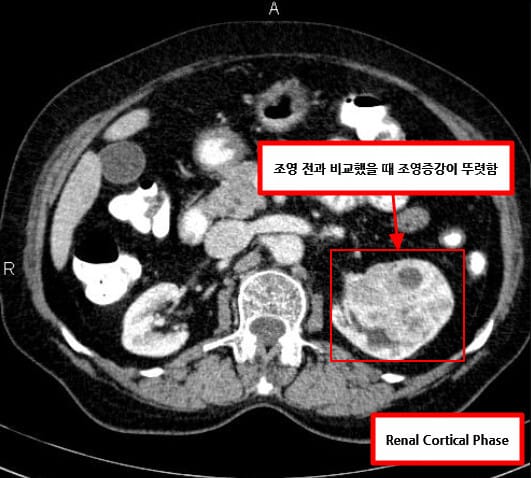

| 🔵 조영증강 CT (CT urography) |

| 가장 중요한 검사로, 고형성 종괴, 중심 괴사, 혈관 침범 여부 등을 평가합니다. 조영제 주입 후 비정상 조영 증강을 보이는 경우 악성 가능성 높습니다. |

영상소견 정리

CT/ MRI 소견

조영증강 영상에서 고형성 종괴 + 중심 괴사, 혈관 침범

| CT/ MRI 소견 |

| ✅ 조영증강 고형 종괴 |

| CT에서 조영제 주입 시 병변이 비정상적으로 밝게 조영되며, 실질보다 높은 밀도 |